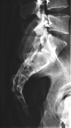

Dieses weltweit einmalige Phantom bietet erstklassige Übungsmöglichkeiten für die Lagerungs- und Einstelltechnik in der Projektions-Radiographie und gehört eigentlich zur Grundausstattung jeder Röntgen-Ausbildungsstätte. Das Phantom enthält ein natürliches menschliches Skelett sowie die Umrisse von Kehlkopf, Lunge, Herz und Nieren (Organe erscheinen als Schatten auf den Röntgenbildern), dadurch können mit dem Phantom echte Röntgenaufnahmen wie beim Patienten gemacht werden. Durch die Verwendung des echten Skeletts können Leitstrukturen im Knochen erkannt werden, was bei Kunststoffskeletten nicht möglich ist. Bei der Montage des Phantoms wird besonderer Wert auf die Darstellung der Gelenkspalte gelegt. Die Gelenke sind voll beweglich montiert, und ermöglichen die Lagerung in den normalen Röntgenpositionen (z.B. Froschposition, Pro- und Supination des Unterarms). Die Arme können nach oben bewegt werden, so dass das Modell auch für alle knöchernen Untersuchungen im CT verwendet werden kann. Bei jedem Phantom handelt es sich um ein handgefertigtes Unikat, welches sich in Größe und Ausführung unterscheiden kann. Je nach Modell können pathologische Befunde vorhanden sein, die äußere Erscheinung kann sich je nach Größe des Modells unterscheiden. Die neue Ausführung dieses Modells wurde in Zusammenarbeit mit einer namhaften deutschen Schule für Med. Techn. Radiologieassistenten komplett überarbeitet und erfüllt alle Anforderungen für die Ausbildung. Der Verkauf dieses Phantoms erfolgt nur gegen Nachweis der medizinischen Verwendung. Natürliche Größe.